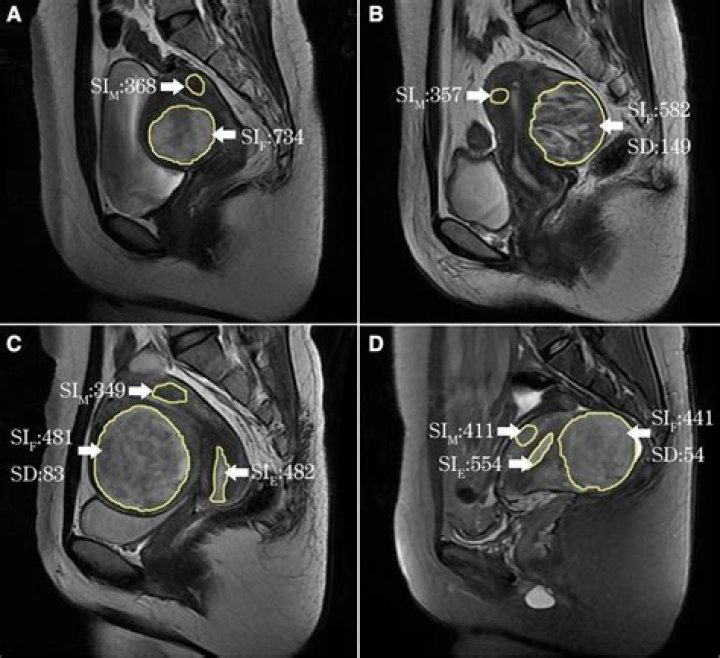

Will an MRI show ovarian cysts?